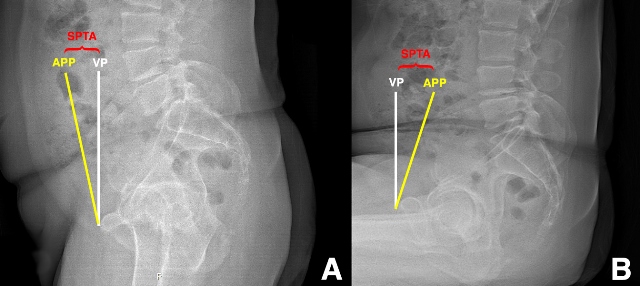

Ranawat et al. [9] explored the effects of fixed versus flexible spinopelvic relationships on the functional position of the acetabular component in a cohort of primary THA patients using frontal and lateral radiographs acquired in standing and sitting positions (Figure 1A-B). Compared to those patients with relatively flexible spinopelvic relationships, they defined those with more rigid spinopelvic motion as having less than 10 degrees of change in sagittal pelvic tilt from standing to sitting position. Of the 68 patients included for the study, over 70% had evidence of spinal pathology and 25% met the authors’ definition of having a stiff spine, or “fixed pelvis”.  Flexible patients exhibited slight anterior sagittal pelvic tilt in standing to more substantial posterior tilt in sitting, the effect of which increased functional anteversion of the acetabular component by 0.75 degrees per degree of posterior tilt as they sat. Presumably, increased functional anteversion is protective against posterior dislocation during sitting. For patients with fixed spines, there was significantly less functional acetabular anteversion in the sitting position (i.e. less protection against posterior THA instability). The authors conclude that a dynamic assessment of spinopelvic motion should be part of the preoperative planning for THA. For THA patients with flexible spines, they recommend reproducing native acetabular anteversion, and they speculate that patients with flexible spines do not necessarily require pelvic tilt-adjusted anteversion, as prior publications have suggested [5]. However, they recommend increasing acetabular component anteversion in patients without normal posterior pelvic tilt in sitting.

Figure 1: Preoperative sagittal pelvic tilt angle (SPTA) measurements standing (A) and sitting (B) lateral pelvic radiographs. SPTA, sagittal pelvic tilt angle between the anterior pelvic plane (APP, yellow line connecting the antero-superior iliac spines to the pubis) and the vertical plane (VP, white line). There is anterior sagittal pelvic tilt relative to the VP in standing, and there is posterior sagittal pelvic tilt in sitting.